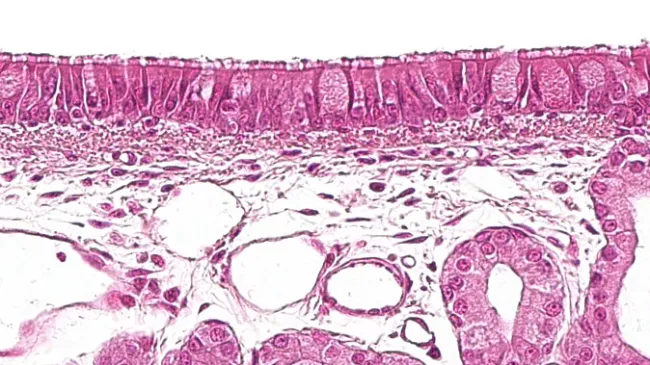

Learn about each of these agents and the various microscopic and macroscopic lesions they cause in the following article.